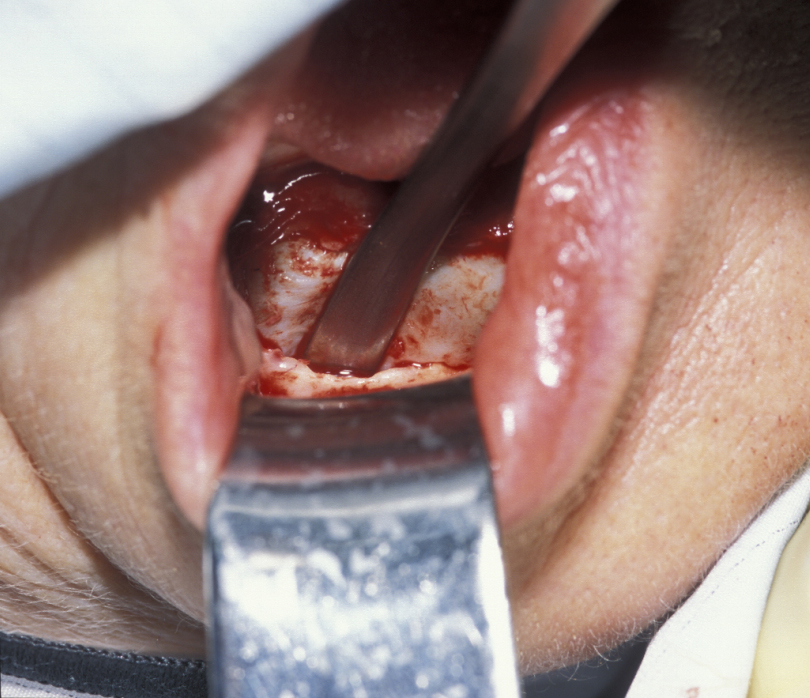

Enucleation involves the stripping away of the cyst lining from the resorbed bony cavity, resulting in a clean ‘hole’ in the bone. This deficit is filled by blood which organises into osteoid and then into new bone. There has never been an evidence-based demonstration of need to graft or fill the defect with synthetic substances. A step by step illustration of the procedure is shown in Figures 1 to 6.

Figure 3: The plane between the cyst lining and the bone cavity is bluntly dissected.

Figure 4: Teasing the cyst by direct traction and dissection delivers the cyst.

Figure 5: The empty bone cavity after removal of the cyst.